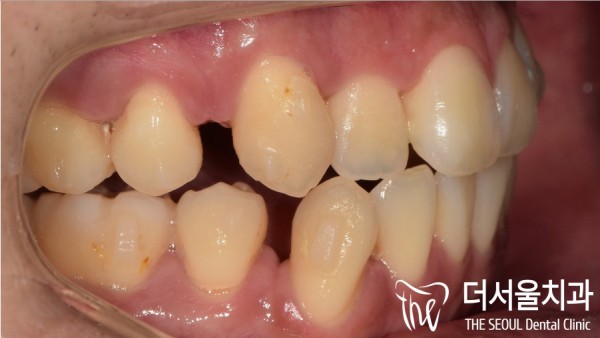

오늘은 돌출입과 함께 정상적으로 교합되지 않는 치아때문에

불편함을 느끼고계셨던 환자분의 인비절라인 교정에 대한 사례를

소개해 드리도록 하겠습니다.

이 환자분은 좌측 두번째 큰 어금니가 아래쪽으로

내려온 느낌이 점점 불편해지셔서 저희 태평역치과 더서울치과를 찾아주셨습니다.

그리고 교합이 맞지 않아 비대칭 상태였는데요.

이렇게되면 장기적으로 턱관절에도 안좋은 영향을 주게된답니다.

생각보다 어금니가 아래쪽으로 많이 내려와 있는것을 확인할 수 있었습니다.

그리고 전반적인 돌출입형태를 보이고 계신것 또한 확인되었습니다.

환자분께선느 어금니 교정과 함께 돌출입과 총생도 개선하고 싶다고하셔서

해당 부분을 투명교정 인비절라인으로 발치교정읕 통해 개선하는 방법으로 교정계획을 수립하였습니다.

#27 어금니를 함입하고 돌출을 개선하고

#37번의 임플란트가 필요하였습니다.